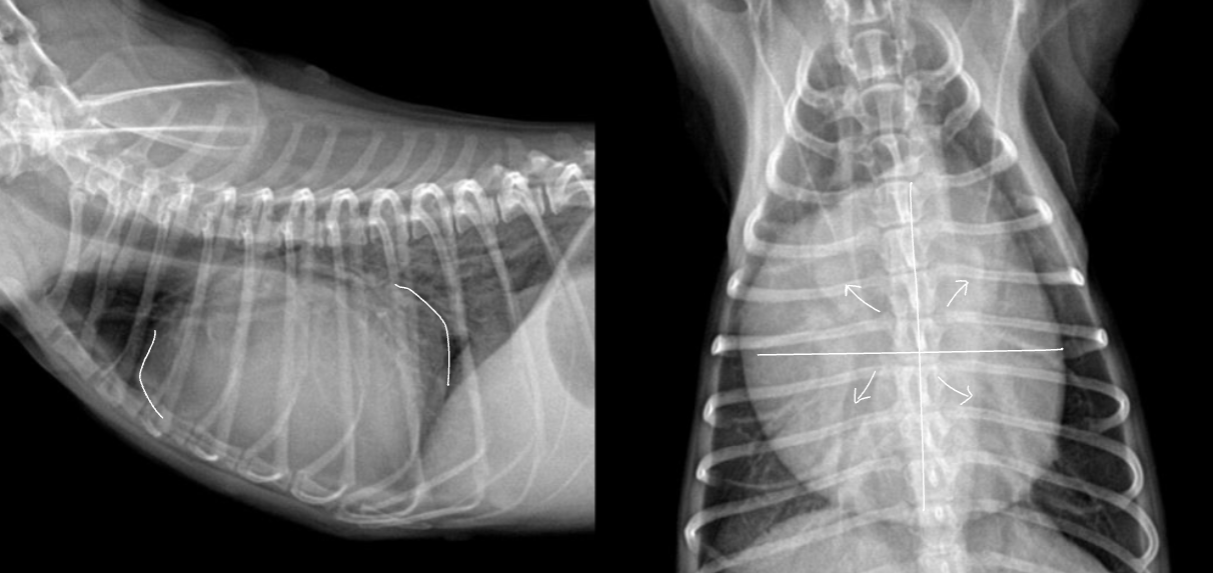

Dilated Cadiomyopathy

| ๋ํ๊ฒฌ์์ commonํ๋ค. Volume overload. Eccentric hypertrophy. - Generalized cardiomegaly - LV Eccentric enlargement - LAE - PV dilation - RCHF ๊ฐ๋ฅ |

| HCM |

| ์ข์ฌ์ค์ด ๋น์ ์์ ์ผ๋ก ๋๊บผ์์ง. ๊ณ ์์ด์์๋ ๋๋ถ๋ถ ์ ์ ์ฑ. LV concentric hypertrophy (X-ray ๊ด์ฐฐ ์ด๋ ค์) Radiographic sign : LAE, valentine shaped heart |